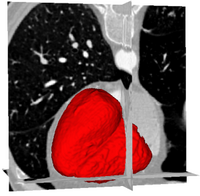

Ventricles Segmentation for Diagnosis of Cardiac DiseasesThis work presents an automatic method for extracting the myocardial wall of the left and right ventricles from cardiac CT images. In the method, the left and right ven- tricles are located sequentially, in which each ventricle is detected by first identifying the endocardial surface and then segmenting the epicardial surface. More... New: L. Zhu, Y. Gao, V. Appia, A. Yezzi, C. Arepalli , A. Stillman, and A. Tannenbaum. Automatic Extraction of the Myocardial Wall from CT Images using Shape Segmentation and Variational Region Growing, IEEE Transaction on Biomedical Engineering, vol. 60, no. 10, 2013. | |